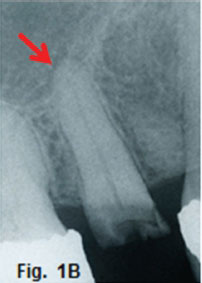

Fig 1A and B demonstrates an example of an infection of the canine fossa. The infection is commonly caused by the spread of infection from the maxillary canine and premolars. Fig. 1B shows a slight widening of the periodontal ligament space (Red arrow) suggestive of an apical infection. The canine fossa contains considerable connective tissue and fat, which allow accumulation of tissue fluids and pus between. These infections are most often controlled with antibiotics. However if the infection becomes localised, drainage is indicated. In the second case the patient presented for treatment of a lesion of her right mandible (Fig. 2A) which have been present for many months. The cropped radiograph (Fig.2B) demonstrates two root rests of a molar tooth with a draining sinus perforating the cortex (green arrows). After removing the root rests the lesion disappeared spontaneously within three weeks. A diagnosis of a cutaneous odontogenic fistula was made. The third case, a 12-year old boy, presented with a six year history of a septic draining sinus in the right temporal region (Fig. 3A).The patient had had his first infection of the right infra orbital region when he was one day old. Since that time he had five surgical procedures, which included craniotomies of the temporal region as well as a condylectomy for treatment of an ankyloses of the right TMJ. On examination, a 2x2 cm opening was found in the right temporal region; (Fig.3B). The patient could not open his mouth. The cropped pantomograph (Fig. 3C) showed an apical cystic lesion in the 46 region (yellow arrow), previous attempted condylectomy scar (black arrow) and the presence of a temporal sinus tract (blue arrow). The first surgical procedure involved removal of all infected focal areas of dental origin. This resulted in uneventful healing of the sinus tract (Fig.3D). A successful condylectomy was performed a few weeks later. Orofacial fistulas are not common but intraoral sinus tracts due to dental infections are common. If the tooth causing the problem is treated endodontically or by extraction the lesion will resolve.